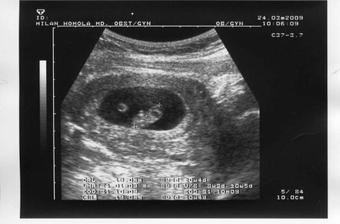

2.3. UTZ - tak vše ještě jednou potvrzeno, je tam 13,6 mm velká bublinka a žloutkový váček, odpovídáme 5 + 2 tt a dostali jsme i fotečku, za 14 dní zase na UTZ a to už by nám mělo tlouct i srdíčko.